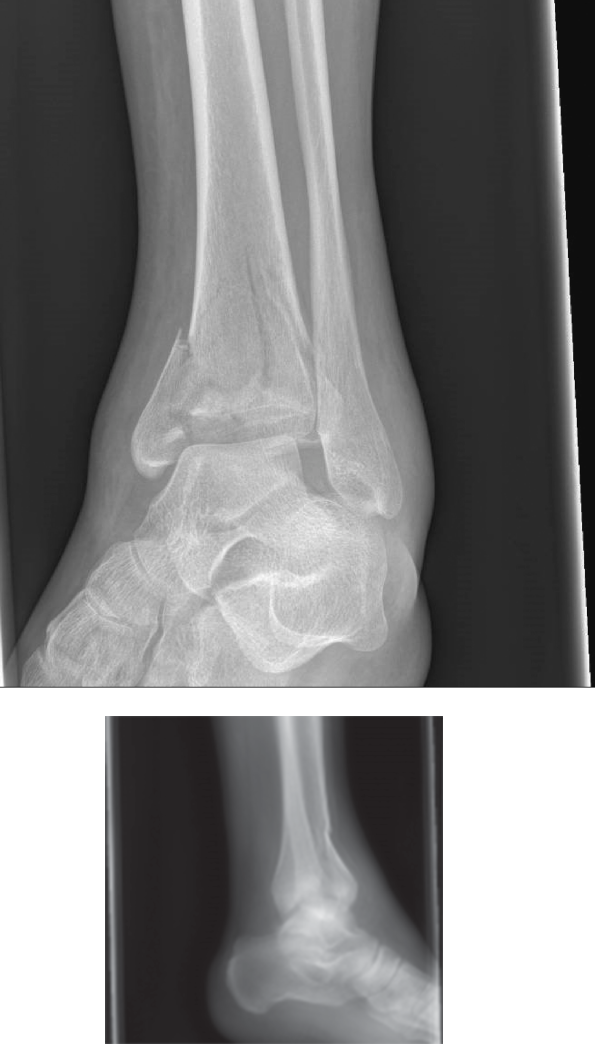

Standard Radiographic Evaluation

The initial radiographic series includes orthogonal views of the tibia and fibula, as well as dedicated Anteroposterior, Lateral, and Mortise views of the ankle joint. The radiographs reveal a highly comminuted, complete articular fracture of the distal tibia. The fracture pattern demonstrates significant metaphyseal comminution with a varus collapse of the distal articular block. The fibula is fractured at the level of the syndesmosis, exhibiting a short oblique pattern consistent with a supination-adduction or high-energy axial loading mechanism. The talus is proximally migrated and driven into the central portion of the tibial plafond, creating a massive central die-punch fragment. The medial malleolus is fractured at its base with vertical extension, and there is gross displacement of the anterolateral (Chaput) fragment. The disruption of the syndesmotic ligaments is evident by the widening of the tibiofibular clear space and the loss of the normal tibiofibular overlap. These standard radiographs provide a macroscopic overview of the injury, confirming the diagnosis of a severe pilon fracture and dictating the immediate need for damage control orthopedics.